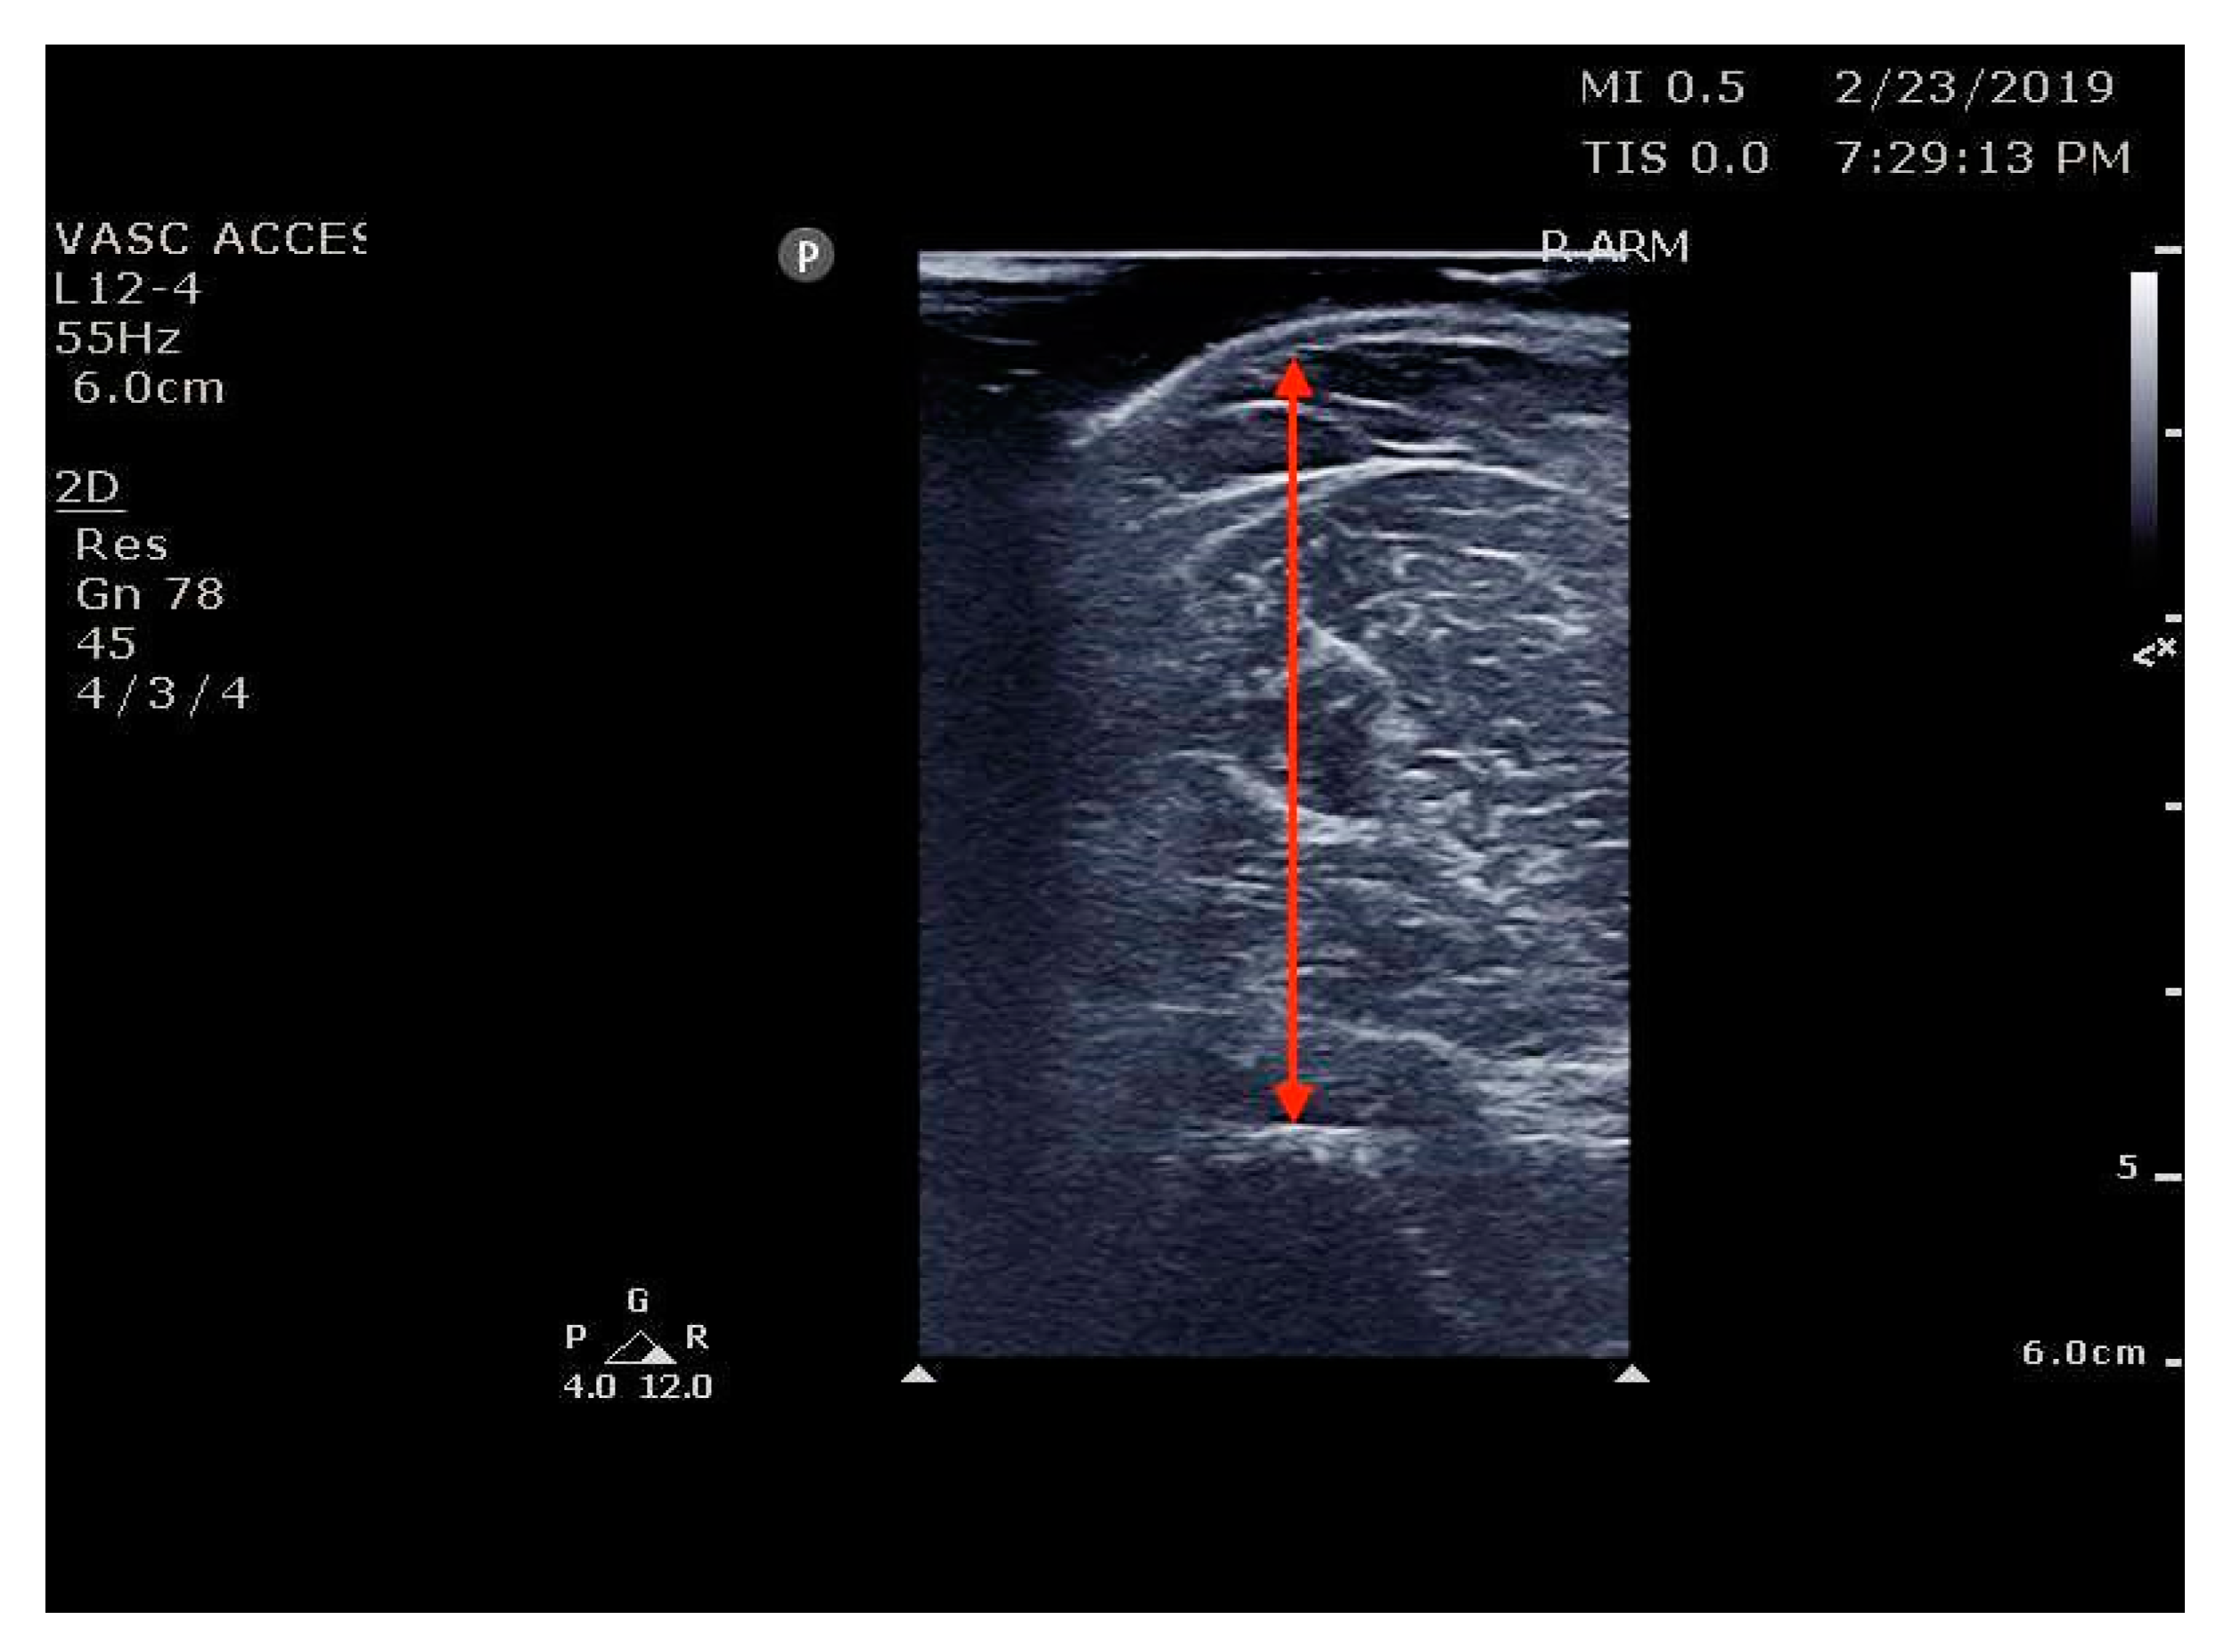

- Madden, K.M.; Feldman, B.; Arishenkoff, S.; Meneilly, G.S. A rapid point-of-care ultrasound marker for muscle mass and muscle strength in older adults. Age Ageing 2021, 50, 505–510. [Google Scholar] [CrossRef] [PubMed]

- Hogenbirk, R.N.M.; Viddeleer, A.R.; Hentzen, J.E.K.R.; van der Plas, W.Y.; van der Schans, C.P.; de Bock, G.H.; Kruijff, S.; Klaase, J.M. Thickness of Biceps and Quadriceps Femoris Muscle Measured Using Point-of-Care Ultrasound as a Representation of Total Skeletal Muscle Mass. J. Clin. Med. 2022, 11, 6606. [Google Scholar] [CrossRef] [PubMed]